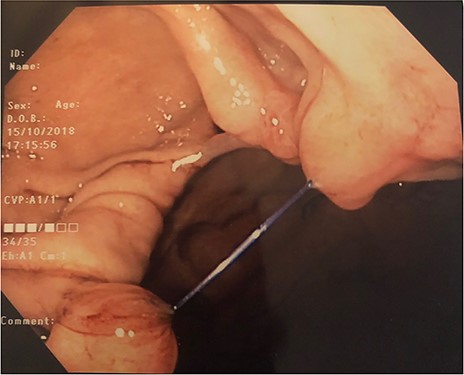

Gastroscopy was performed 2 weeks pre-surgery and revealed complete dehiscence of ESG sutures (Figs 1 and 2). All visible sutures and clips were removed endoscopically.

Endoscopic view during gastroscopy showing dehiscence of endoscopic sleeve gastroplasty sutures. This was taken 2 weeks prior to laparoscopic sleeve gastrectomy

Retroflexed endoscopic view during gastroscopy showing dehiscence of endoscopic sleeve gastroplasty sutures. This was taken 2 weeks prior to laparoscopic sleeve gastrectomy